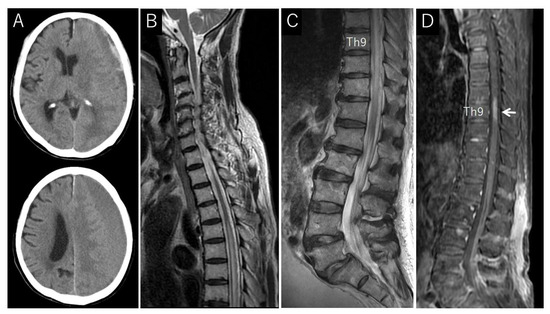

Case Description